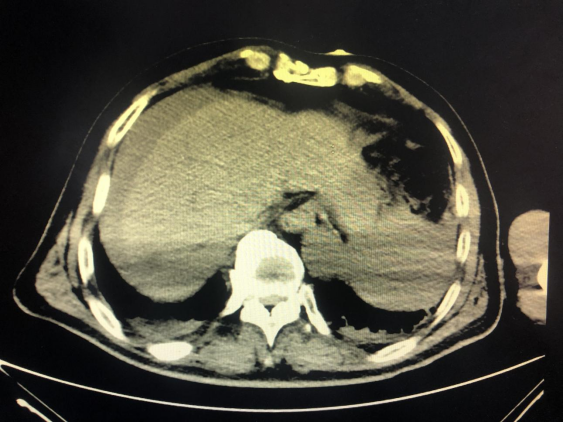

家住哈市道外区的周先生已年过八旬,耄耋高龄的他肝右叶有一大血管瘤(直径约9cm),因有破裂大出血风险,医生建议手术切除。周先生担心自己年龄较大,又有脑梗,且抱有一定侥幸心理,未选择手术治疗。

腹腔内出现大量血性积液